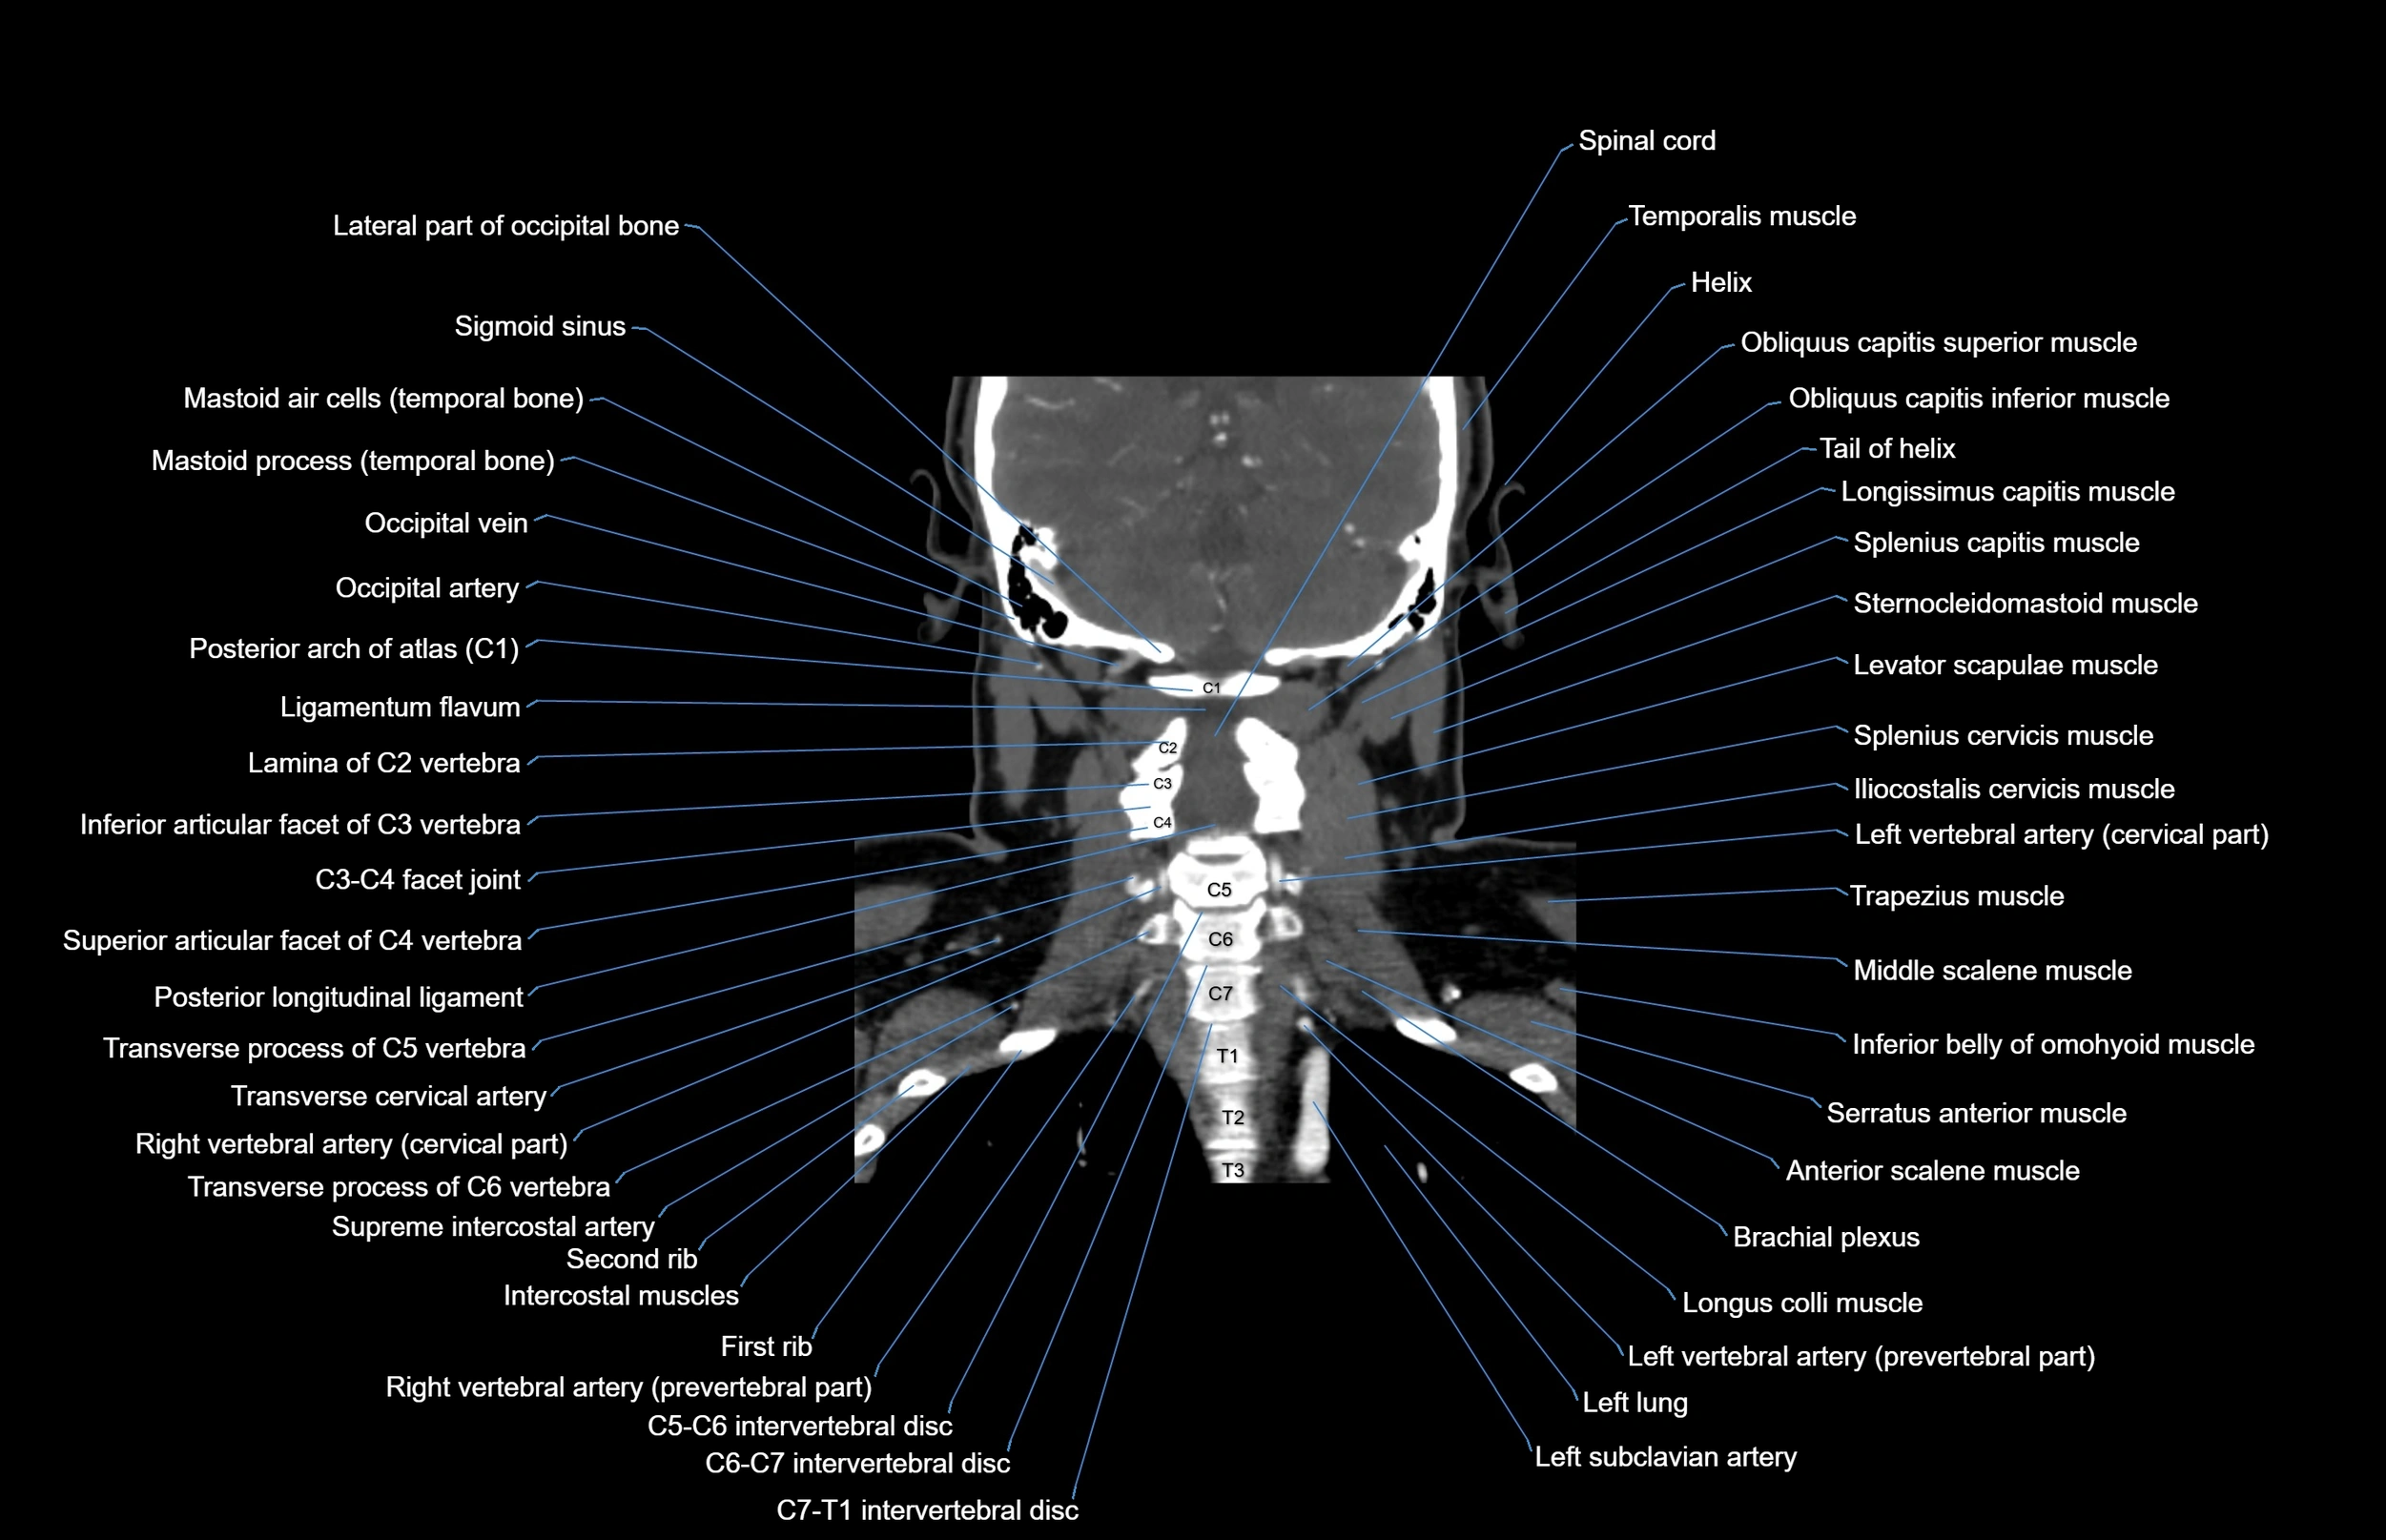

- Iliocostalis cervicis muscle

- Left vertebral artery (cervical part)

- Levator scapulae muscle

- Longissimus capitis muscle

- Posterior arch of atlas

- Posterior longitudinal ligament

- Right subclavian artery

- Right vertebral artery

- Right vertebral artery (atlantic part)

- Right vertebral artery (cervical part)

- Serratus anterior muscle

- Spinal cord

- Splenius cervicis muscle

- Sternocleidomastoid muscle

- Trapezius muscle